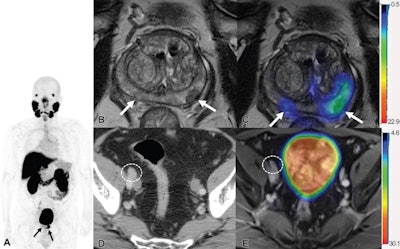

Patients then underwent initial staging with F-18 DCFPyL PET/CT, or PET/MRI, and the researchers compared the intended treatment plan for patients before PET with the treatment plan established after performing PET.

Out of the 108 cases, F-18 DCFPyL PET outperformed conventional imaging by upstaging disease extent in 36 men (33%) and downstaging in seven men (7%). PET with the radiotracer also identified twice as many cases of oligometastatic disease, according to the findings.

PET altered treatment in 24 of 108 (22%) men, with the most frequent treatment change from systemic to local-regional therapy in 10 men, and from local-regional to systemic therapy in nine. Equivocal findings were encountered with PET in one of 108 men, compared with 29 of 108 with conventional imaging (27%).